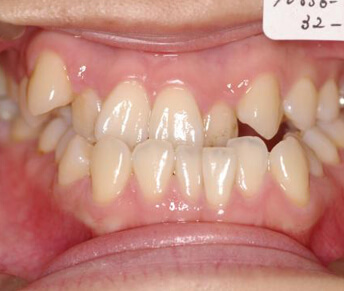

歯列矯正治療には幾種かの装置があります。

装置別のメリット、デメリットを認識し治療に望むことは治療の第一歩であり、それは治療の成果に大きく影響します。

- 見えにくい矯正装置

(セラミック、ブラスチックブラケット)

メリット

- ・装置が目立たない。

デメリット

- ・装置とワイヤーの摩擦抵抗が大きい(滑りが悪い)ので歯が動きにくく、治療期間が長くなる。

- ・装置がセラミックやプラスチックなので金属製に比べ強度が低いので、壊れにくくする為に装置が大きく、違和感が強く口内炎もできやすい。

- ・大きく頑丈に作られていてもやはり強度が低いので装置が割れたり、外れたりする。その度に装置をつけ直す事になり、治療期間が長くなり易い。

- ・装置が壊れやすいので強い力をかける事が難しく、正確に歯をコントロールして良い治療結果得るのが難しい。